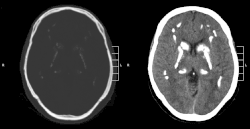

CT scan of characteristic calcifications of the disease

Primary familial brain calcification[1] (PFBC), also known as familial idiopathic basal ganglia calcification (FIBGC) and Fahr's disease,[1] is a rare,[2] genetically dominant or recessive, inherited neurological disorder characterized by abnormal deposits of calcium in areas of the brain that control movement. Through the use of CT scans, calcifications are seen primarily in the basal ganglia and in other areas such as the cerebral cortex.[3]

Brain CT scan is the preferred method of localizing and assessing the extent of cerebral calcifications.

The calcification is usually identified on CT scan but may be visible on plain films of the skull.